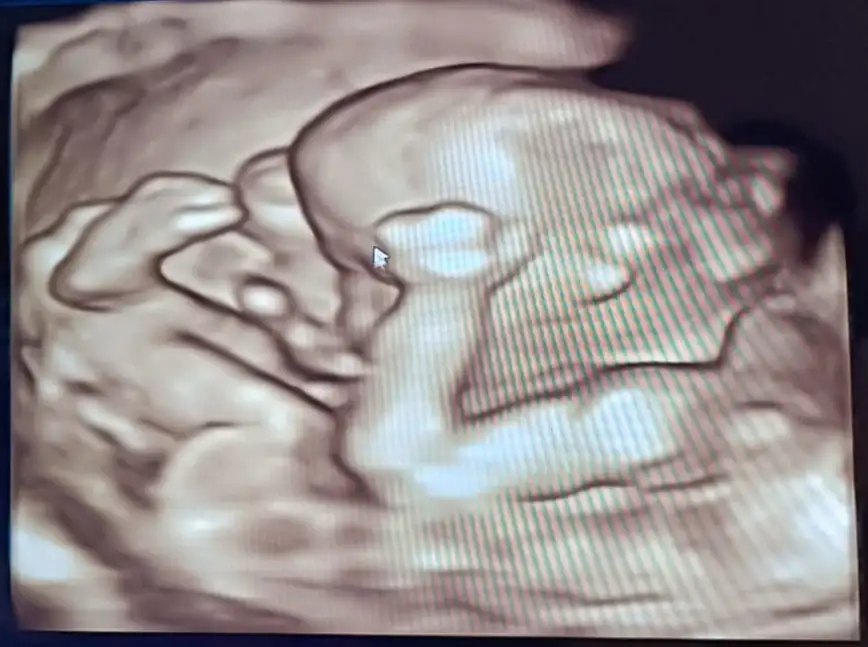

Utangaç olcak galiba yüzünü kapatmış sanırım çok tatlıİyi akşamlar kızlar.. bugün evde temizlik yapıp doktora gittim, bebiş ilk defa böyle iki büklüm duruyordu. Acaba temizlik yaptığım için mi böyle duruyor? Ben mi yanlış bir hareket yapıyorum ki? Bilgisi olan var mı?

Üzüldüm birazUtangaç olcak galiba yüzünü kapatmış sanırım çok tatlı